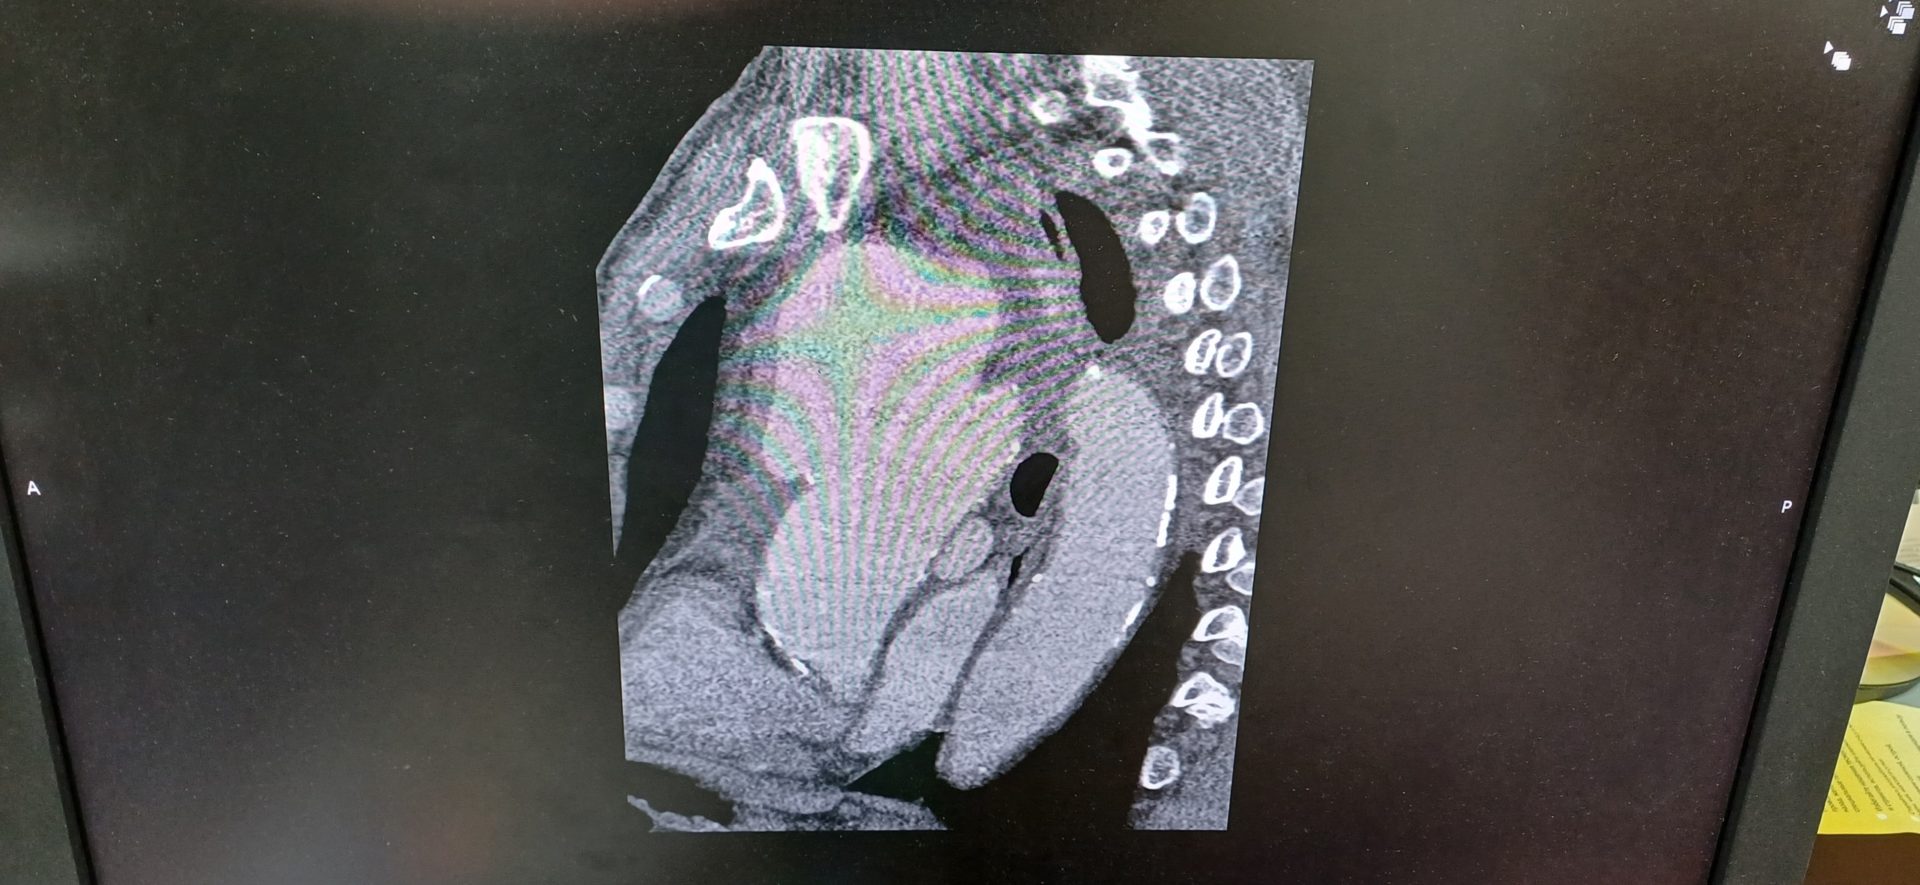

«Компьютерная томограмма подтвердила выпячивание аорты размером 9 на 9 сантиметров. Гигантская мешотчатая аневризма, больше, чем гусиное яйцо. Она сдавливала все близлежащие органы и ткани: трахею, бронхи, верхнюю полую вену. Уникальный случай. Аневризмы таких размеров встречаются не часто», – отмечает заведующий отделением №5 Рязанского кардиодиспансера Сергей Загородний.